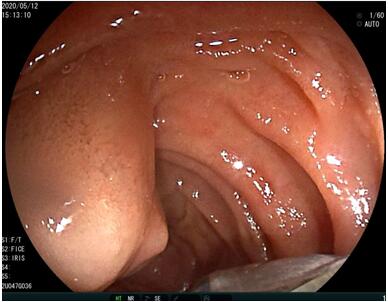

69歲王姓患者,因“發(fā)現(xiàn)無痛性黃疸1月”入院,根據(jù)患者病史,患者診斷傾向于壺腹部腫瘤所致梗阻性黃疸。予以完善腹部CT及上腹部MRI加MRCP均顯示肝內(nèi)外膽管擴(kuò)張,未發(fā)現(xiàn)明顯膽管,胰腺及十二指腸乳頭部腫瘤,且患者CA199正常。以前醫(yī)院未引進(jìn)超聲內(nèi)鏡,這類患者到此就遇到診斷瓶頸。此患者經(jīng)過消化內(nèi)科張丹霞副主任醫(yī)師完善超聲內(nèi)鏡檢查后,可以清楚顯示膽總管下段壁內(nèi)軟組織占位?;颊咄ㄟ^超聲內(nèi)鏡檢查診斷明確,轉(zhuǎn)至肝膽外科行手術(shù)治療。

超聲胃鏡圖片